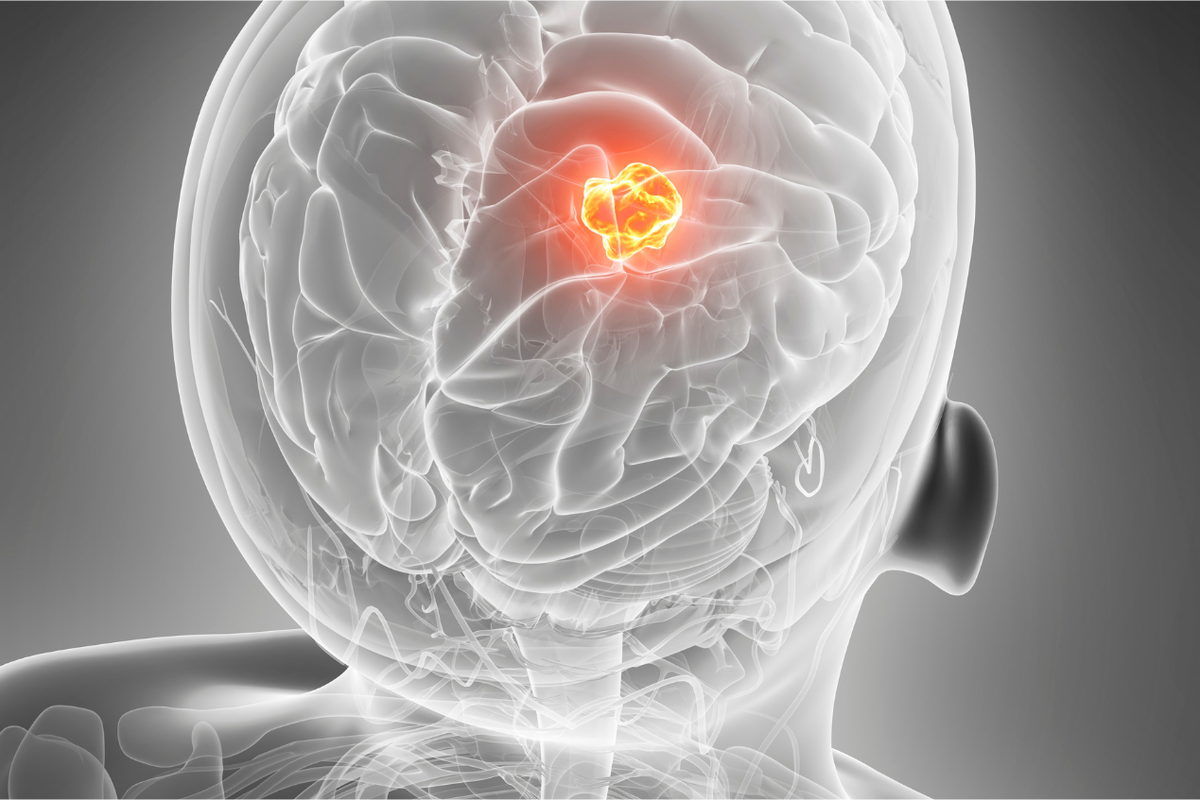

IDNWATCH – Para peneliti mengungkapkan temuan terbaru yang berpotensi menjadi titik terang dalam perawatan glioblastoma, salah satu jenis kanker otak paling agresif dan mematikan. Studi terkini menunjukkan bahwa penerapan diet khusus, yakni diet ketogenik yang dikombinasikan dengan pembatasan kalori, dapat menciptakan lingkungan metabolik yang “tidak nyaman” bagi sel kanker untuk berkembang, sehingga meningkatkan efektivitas pengobatan standar.

Hasil Studi: Memperlambat Pertumbuhan Tumor dan Perpanjang Harapan Hidup

Temuan yang dipublikasikan dalam jurnal ilmiah terkemuka ini menunjukkan hasil yang menjanjikan. Pada model preklinis, kelompok yang menerapkan protokol diet khusus ini menunjukkan pertumbuhan tumor yang secara signifikan lebih lambat dibandingkan dengan kelompok yang menjalani diet normal. Yang lebih penting, terapi kombinasi antara pengobatan standar (seperti radiasi dan kemoterapi) dengan diet ini dikaitkan dengan peningkatan harapan hidup.

Meskipun penelitian lebih lanjut dan uji klinis skala besar masih sangat diperlukan, temuan awal ini memberikan harapan baru sebagai terapi pendamping (adjuvant therapy) yang potensial bagi pasien glioblastoma. Pendekatan ini menawarkan strategi yang relatif non-invasif untuk meningkatkan hasil pengobatan.